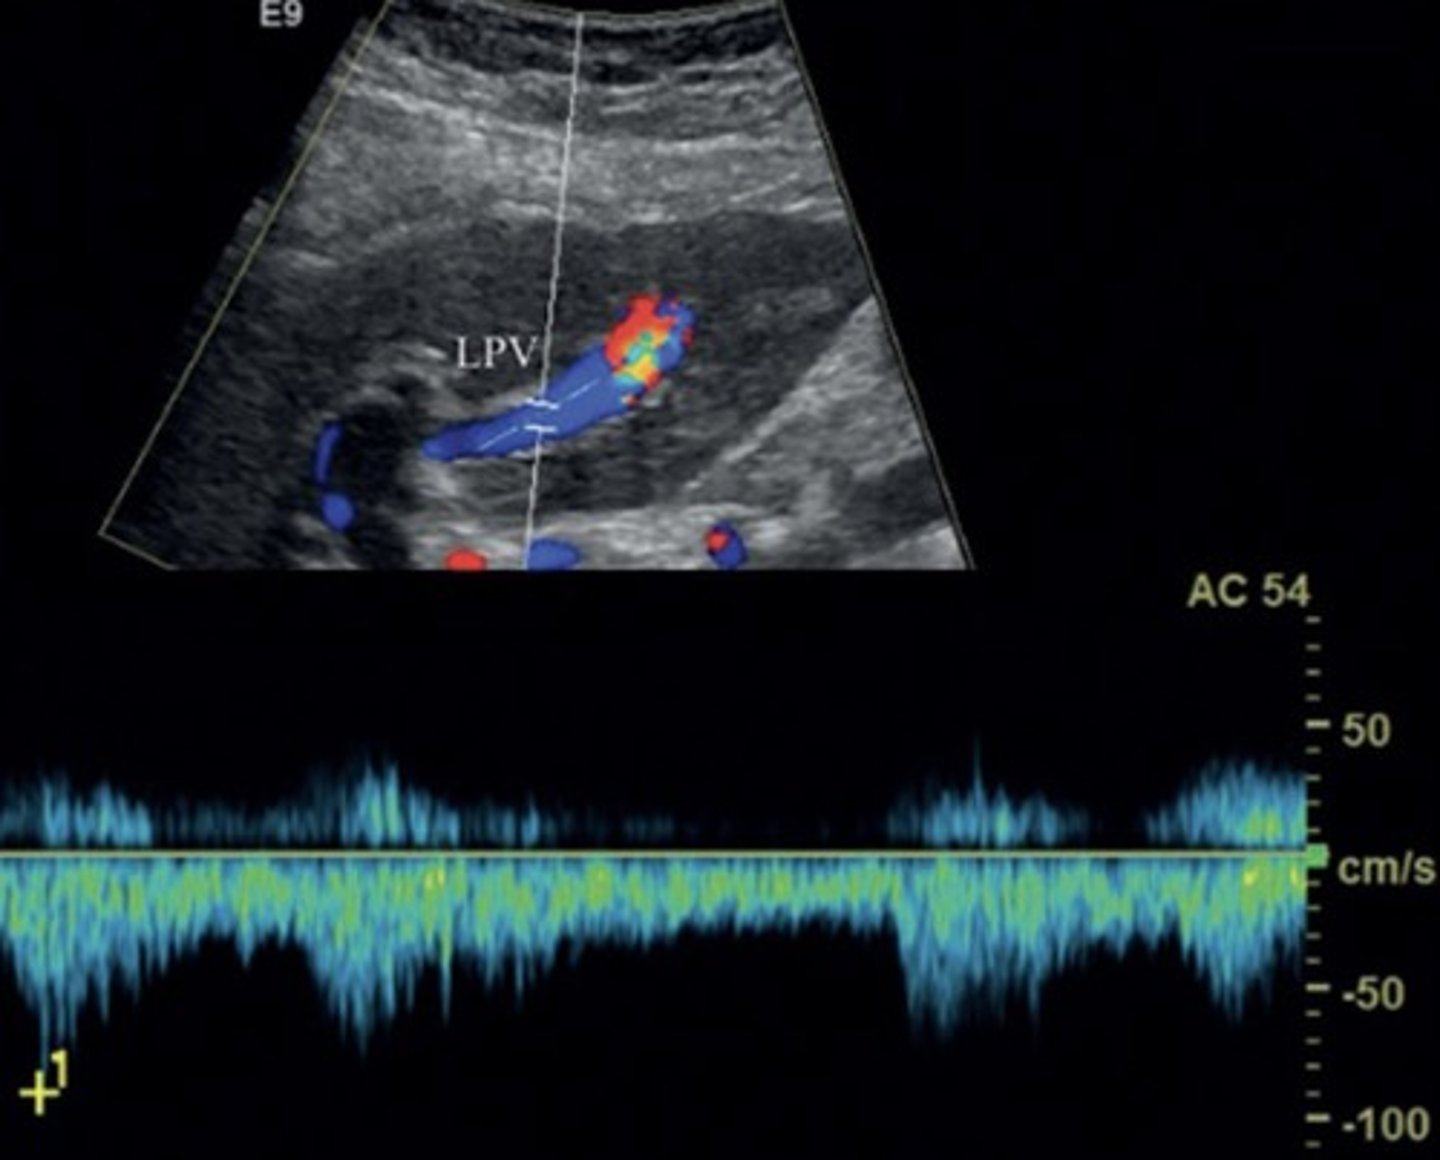

Main Portal Vein Doppler Waveform

Monophasic continuous waveform

Hepatopetal flow (antegrade flow)

Portal HTN Doppler Findings

Slow, hepatofugal flow in portal vein